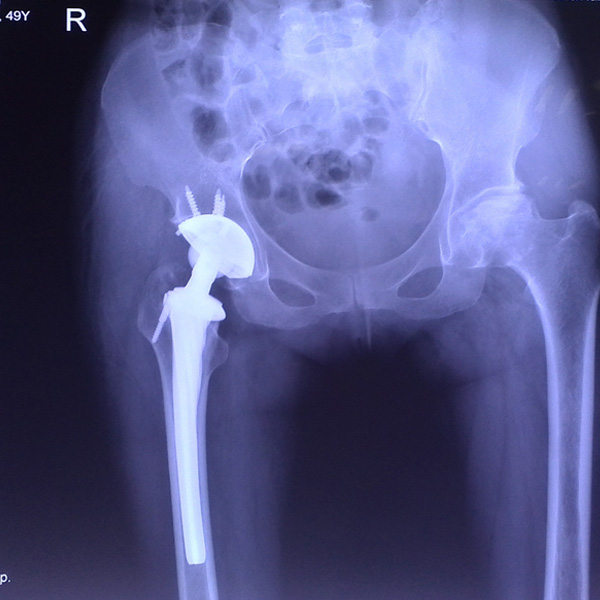

• 右側全髖關節(jié)置換右側全髖關節(jié)置換手術后手術前

右側全髖關節(jié)置換

患者姜某某,女50歲,診斷為“股骨頭壞死”,右側髖關節(jié)疼痛到不能生活自理。經平臺推薦到哈爾濱醫(yī)科大學附屬第二醫(yī)院骨關節(jié)科就診,患者想......